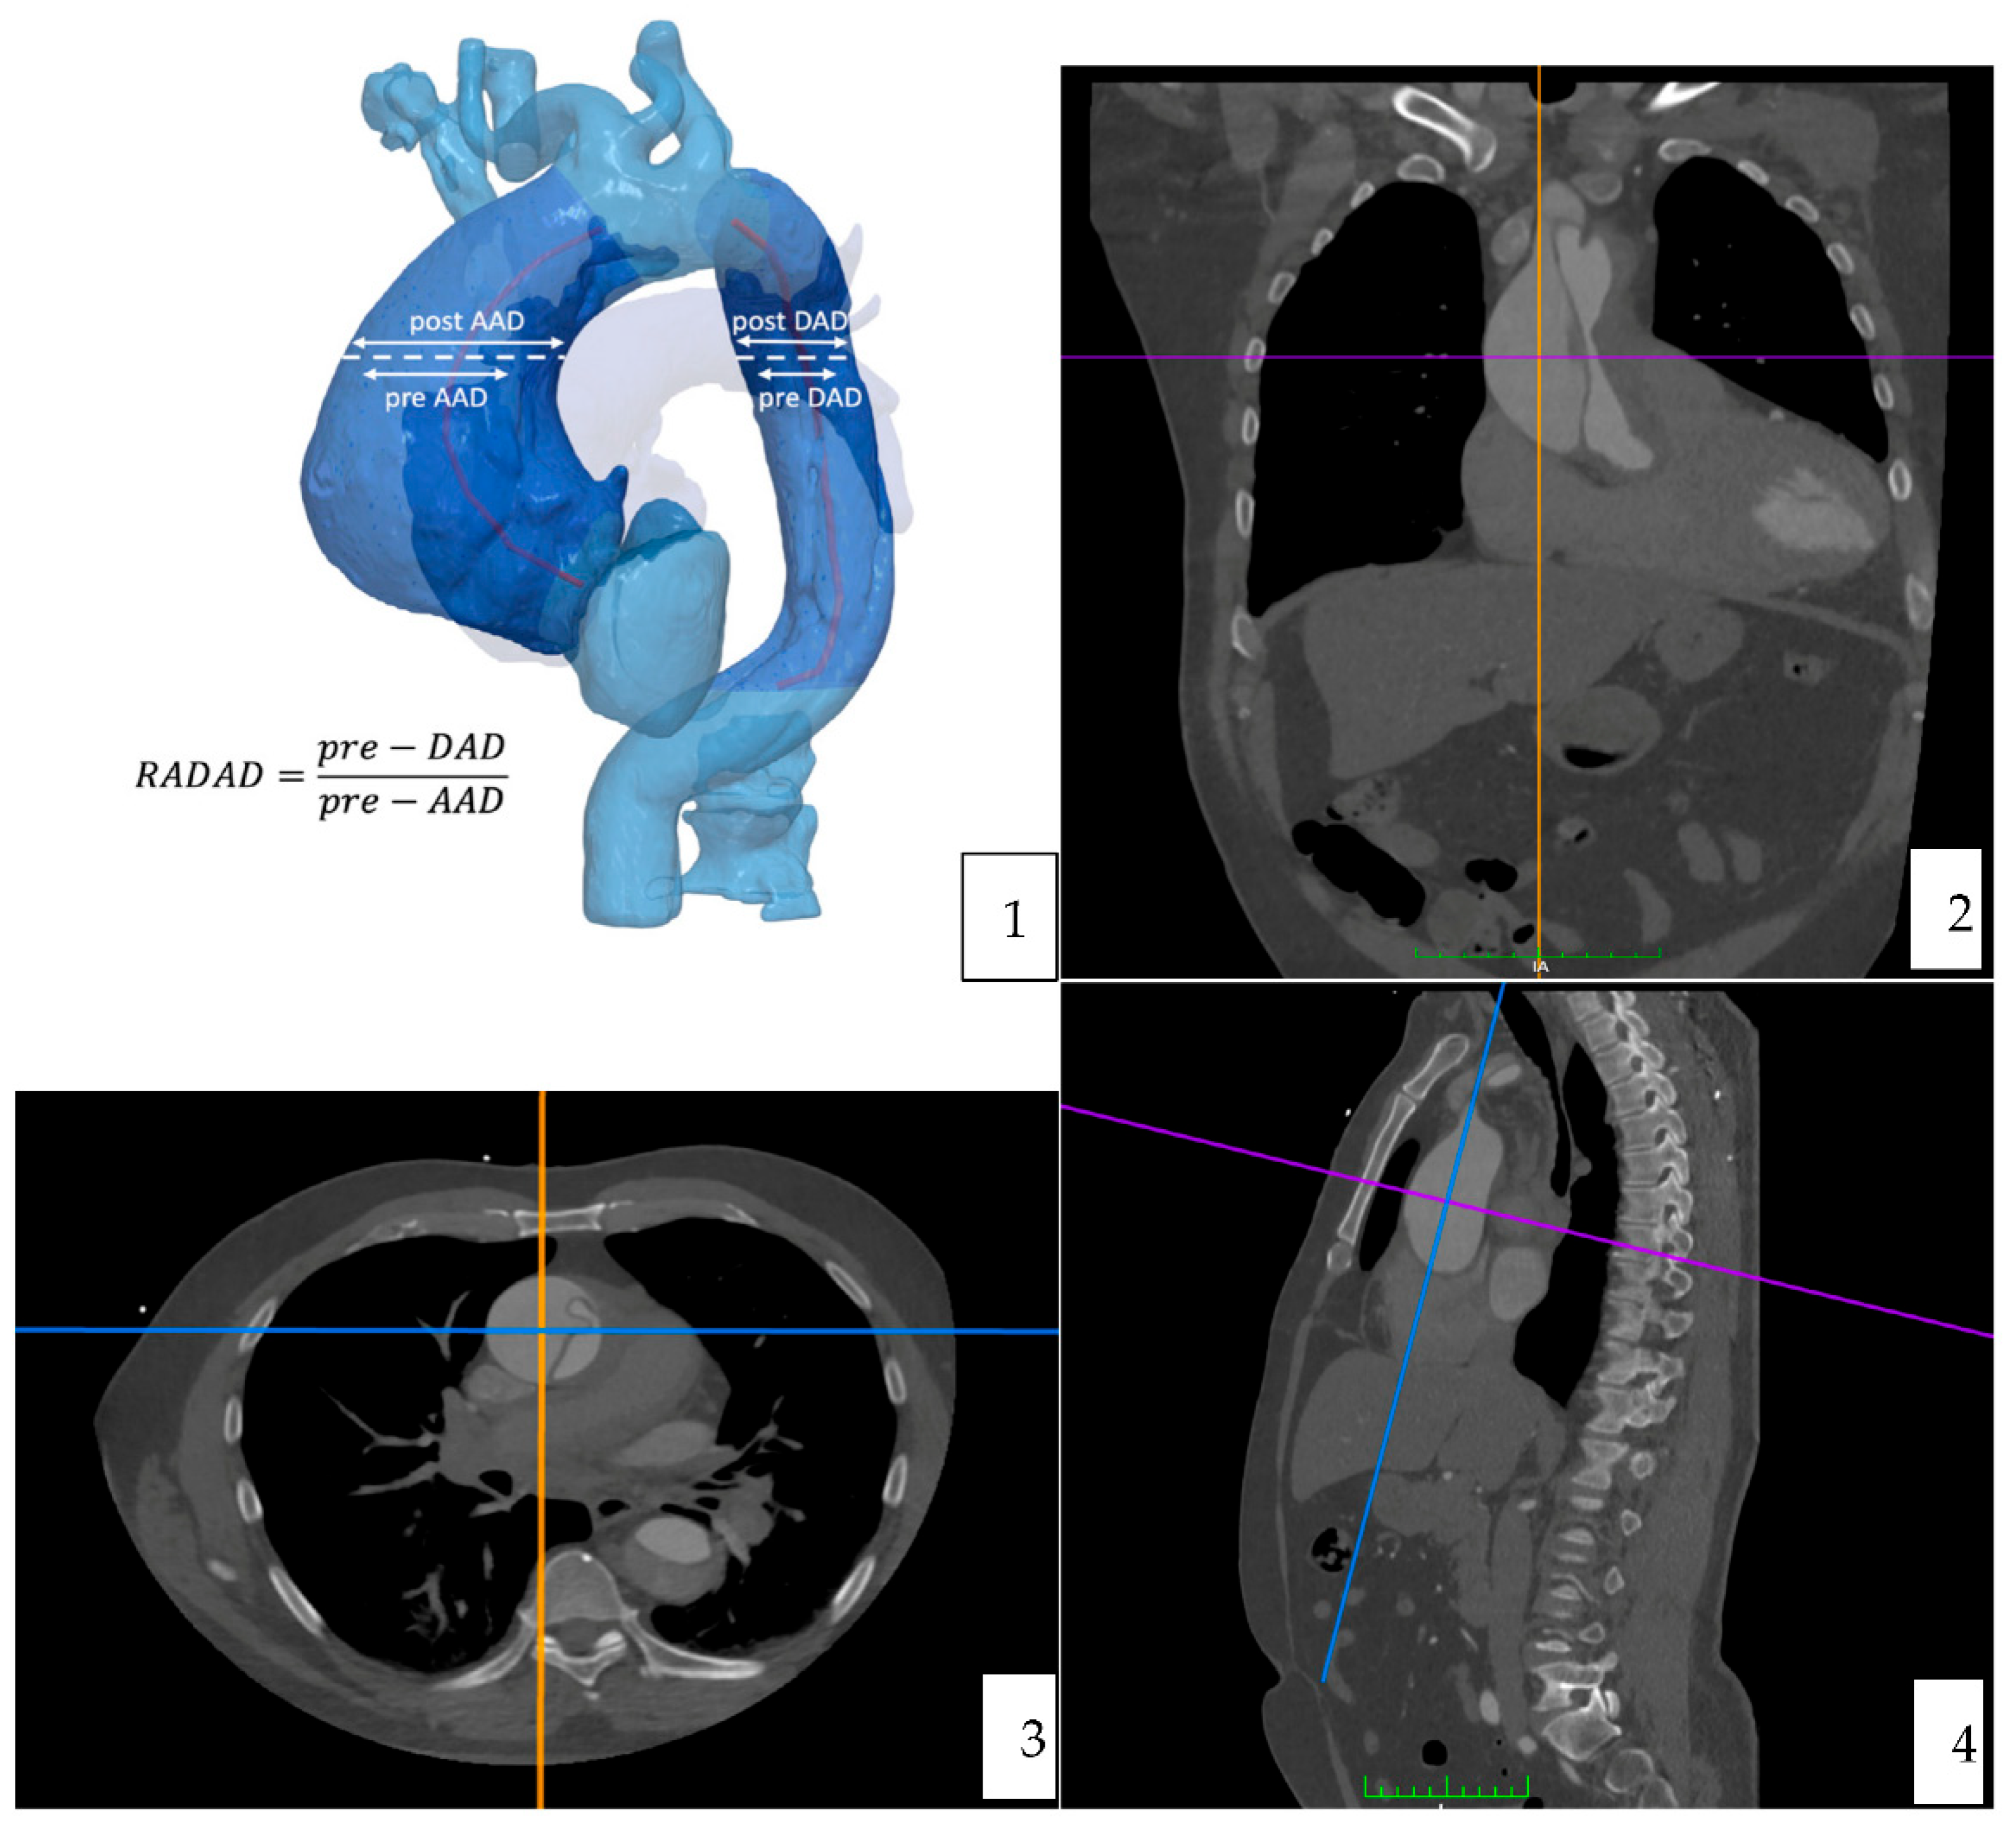

Computer tomography angiography studies were analyzed using the curved multiplane reformats with the DICOM viewer OsiriX vd.12.01. Measures were manually taken, in an orthogonal plan (sagittal, axial and coronal). A reference point to do all the measures was determined at the level of the pulmonary artery bifurcation [Figure 2] [Figure 3].

The maximal diameter (including the false lumen) of the ascending and descending aorta was measured in two perpendicular planes (anteroposterior and medio-lateral) and the sphericity index was calculated.

Figure 2. Imaging process and methodology. (1) 3D Schematization. (2–4) Osirix © curved multiplane reformats, orthogonal plan (independently for AA and DA).